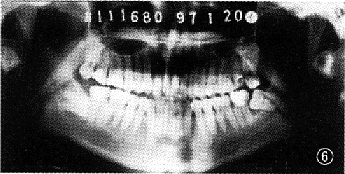

间斜向后下骨折伴右髁突高位骨折 图5 病例1 小型钛板固定中线左侧斜行骨折,颌间制动10d后,弹力牵引配合张口训练 图6 病例2 左下颌角骨折 图7 病例2 左下颌角骨折,拔除阻生牙,小型钛板固内固定,未行颌间结轧 图8 病例2 术后3个月复查,骨折线已明显愈合改建